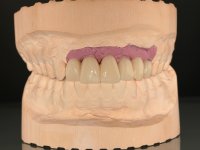

The diagnostic wax-up enclose the possibility to include, or not, gum-shade ceramics to rehabilitate the interdental papillae. This two possibilities were presented to the patient due to the bone regeneration unpredictability (in our opinion), mainly vertically.

The wax-up allowed us to do a mock-up that worked also as a radiological template. The CT-scan was imported to an implant planning software where three dental implants were simulated, and a surgical guide developed.

10 weeks after the surgery, a first impression was done to do a CAD-CAM provisional bridge (based on the diagnostic wax-up), that worked the soft tissue architecture during two months. This architecture was copied in a second impression by individualizing the impression copings in their emerging profile.

The working model was scanned and the dental technician developed a zirconia framework based on the diagnostic wax-up. This framework try-in was done, the perfect fit was assessed, and a final impression was done with a light silicone.

The bridge was finally placed with a progressive screwing to allow the tissue to accommodate the pressure of the pontics and the abutments emergency profiles.